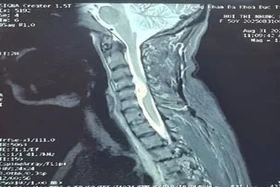

baophutho.vn Ngày 9/9, các bác sĩ Bệnh viện Đa khoa Hòa Bình vừa thực hiện thành công ca mổ lấy khối u màng tủy sống vùng cổ C4/5 – loại u hiếm, vị trí đặc...